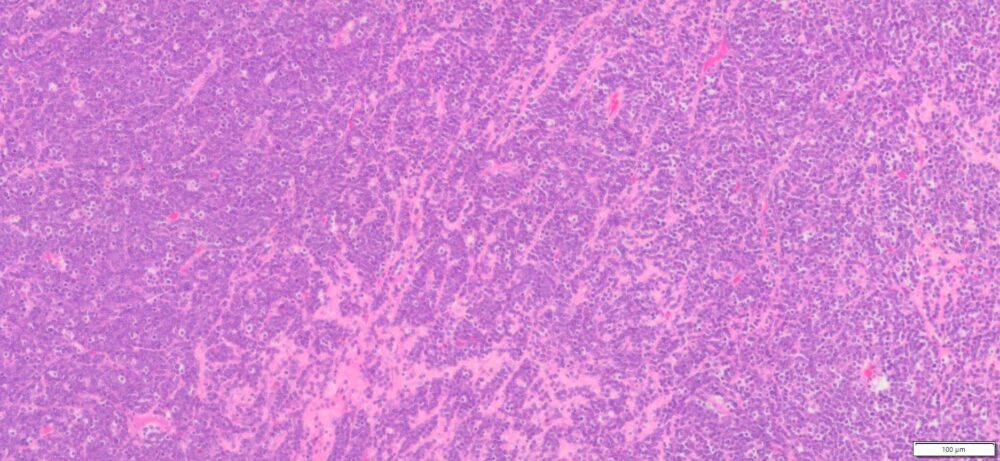

| HumanOvary | Human Ovary B-Lymphoblastic leukemia (ALL) | Male/19 | 90% | N/A | N/A | Diffusely (+): PAX-5,CD10, TdT

Weak (+) : CD79,CD34 and CD45 Neg: CD20,CD3 and MPO |